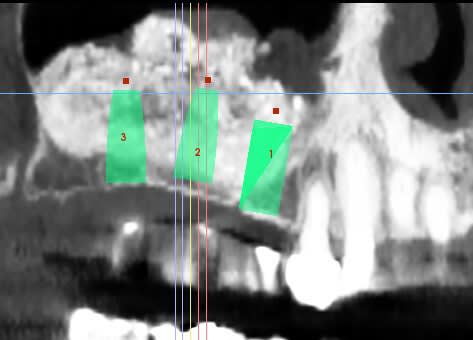

patiente ayant été implantée il y a 12 jours et toujours mal

le sinus lift a été pratiqué il y a 8 mois

j'avais repéré une perf, bien apparente, que j'ai protégée avec une Biogide

j'ai appris à mes dépens qu'un train peut en cacher un autre, savoir

une autre perf plus post, et donc quand je me suis rendu compte que le BM passait dans la deuxième perf,

j'ai interrompu la chir, ce qui explique la présence de lacunes

les implants ont été posés sans problème, et le BM était bien dense

ce qui m'ennuie ce sont les douleurs 12 jours après l'implantation